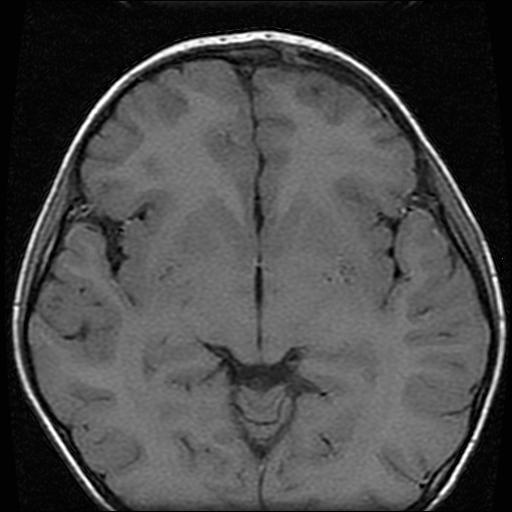

6岁小儿,左侧视神经瘤术后。现左侧视力减退。